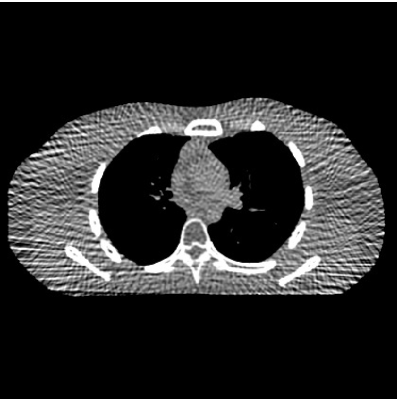

This paper was inspired by a simple observation related to our recent study [34]: for the penalized weighted-least squares (PWLS) reconstruction method using prior with a learned ST (PWLS-ST-) [34], the sparsification error histograms match a Laplace distribution over the iterations; see Fig. 1. The question then arises, “Does the learned prior experience model mismatch in testing stage?” To answer this question, we aim to investigate learned STs for regularization. This paper

The term denotes a -based sparsification error [3, 4, 5]. We expect to be more robust to sparsity model mismatch than the -based sparsification error used in [34, 36]. Fig. 1 shows histograms of sparsification error at different outer iterations of the PWLS-ST- method. Over the iterations, the sparsification error histograms appear more like a Laplace distribution than a Gaussian distribution. This observation suggests that the proposed prior model is more suitable than the prior model for PWLS-ST-based reconstruction. Section III-B1 shows that the proposed -based sparsification error term, , improves the accuracy of reconstruction compared to the prior model in [34, 36].